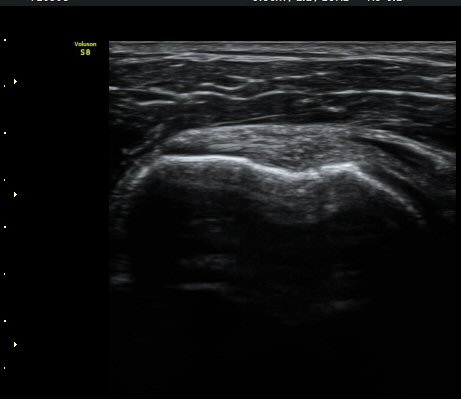

¼ö¾×Àú·ù°¡ °üÂûµÈ´Ù(±×¸² 1, 2). °ß°©ÇÏ±Ù°Ç Á¾´Ü¸é°Ë»ç¿¡¼­ °ß°©ÇϱٰÇÀÇ °üÀý³»ºÎÀ§(±×¸² 3)

¿Í ¼Ò°áÀý »óºÎ(±×¸² 4)¿¡¼­ ƯÀÌ ¼Ò°ßÀ» º¸ÀÌÁö ¾Ê´Â´Ù.